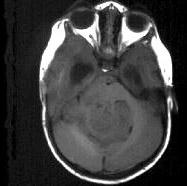

成年男性,头痛、头晕、恶心,病程二年余,结合影像图像选择最可能的诊断()A.脑膜瘤B.星形细胞瘤C.室管膜瘤D.胶质瘤E.畸胎瘤

问题 成年男性,头痛、头晕、恶心,病程二年余,结合影像图像选择最可能的诊断()

选项 A.脑膜瘤 B.星形细胞瘤 C.室管膜瘤 D.胶质瘤 E.畸胎瘤

答案 C